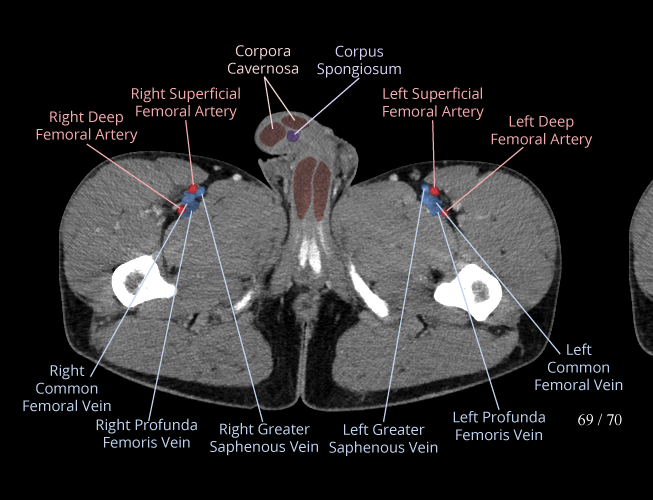

Pelvis

Covers pelvic MRI anatomy.